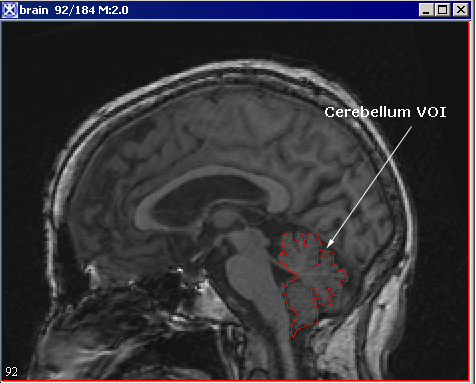

Please, remember that to apply VOIs to images in scripts, you need to create and save the VOIs in advance of creating a script, and then, open and apply the VOIs while you are recording the script. In this example, we will use the VOI which helps extract the cerebellum from the brain image. See Figure 29.

Figure 29. The Cerebellum VOI is delineated on the image

To delineate the VOI on the image, use the Draw Polygon/Polyline VOI tool from the MIPAV toolbar. After you've created the VOI, save it through the VOI >Save VOI command.